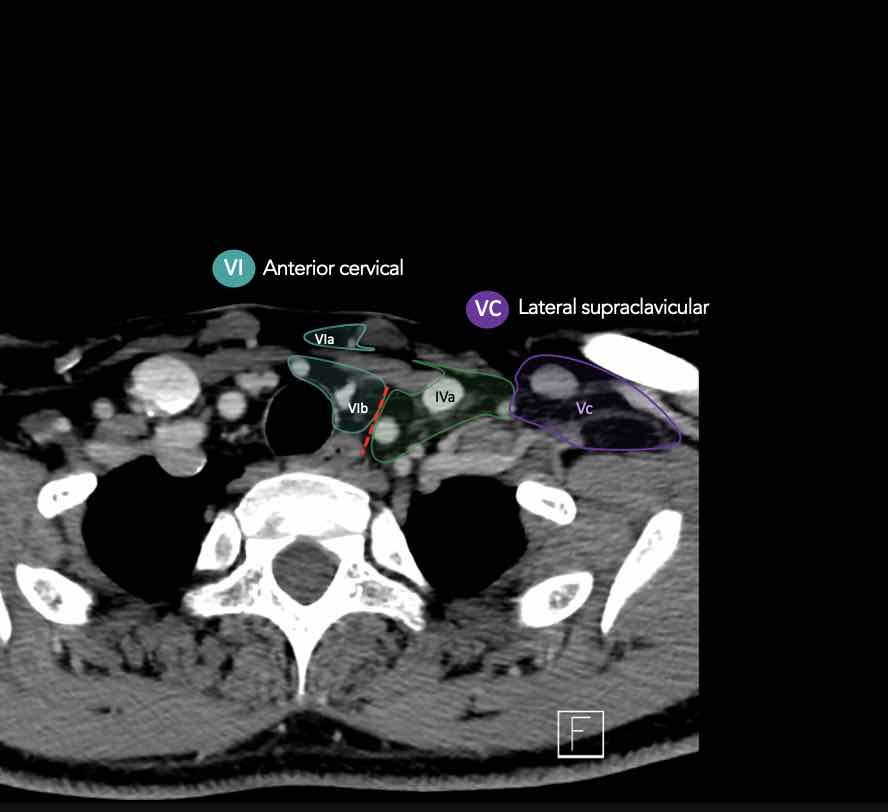

CT Scan Mặt Cắt Ngang (Axial CT)

Các lát cắt CT mặt phẳng ngang tương ứng với hình minh họa tổng quan.

Các lát cắt CT mặt phẳng ngang với hình ảnh chi tiết hơn.

Nhấp vào hình ảnh để phóng to.

V – Tam giác cổ sau và hố thượng đòn

Tầng V chứa các hạch của nhóm tam giác cổ sau nằm ở phía sau cơ ức đòn chũm, xung quanh phần dưới của thần kinh phụ gai sống và các mạch máu cổ ngang.

Các hạch bạch huyết ở tầng V thường liên quan nhất đến các ung thư nguyên phát của vòm hầu, hầu miệng, các cấu trúc da vùng da đầu phía sau và tuyến giáp.

Tầng Vc – Hố thượng đòn

Tầng này chứa các hạch thượng đòn bên nằm trong phần tiếp nối của các hạch tam giác cổ sau (tầng Va và Vb) từ các mạch máu cổ ngang xuống đến giới hạn được xác định tùy ý tại vị trí 2 cm phía trên cán ức.

Tầng này tương ứng một phần với vùng được gọi là hố thượng đòn.

Tầng Vc nhận các bạch mạch hướng tâm từ các hạch tam giác cổ sau (tầng Va và Vb) và thường liên quan hơn đến các khối u vòm hầu [1].

VI – Cổ trước

Tầng này chứa các hạch tĩnh mạch cảnh trước nông (tầng VIa) và các hạch sâu hơn bao gồm hạch trước thanh quản, trước khí quản, cạnh khí quản và hạch thần kinh thanh quản quặt ngược (tầng VIb).